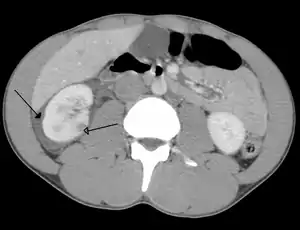

Spleen

Spleen is the most common cause of massive bleeding in blunt abdominal trauma to a solid organ. Spleen is the most commonly injured organ. A laceration of the spleen may be associated with hematoma.[13] Because of the spleen's ability to bleed profusely, a ruptured spleen can be life-threatening, resulting in shock. However, unlike the liver, penetrating trauma to the spleen, pancreas and kidneys do not present as much of an immediate threat of shock unless they lacerate a major blood vessel supplying the organs, such as the renal artery.[5] Fractures of the left lower ribs are associated with spleen lacerations in 20 percent of cases.[9]

Kidneys

The kidneys may also be injured; they are somewhat but not completely protected by the ribs.[6] Kidney lacerations and contusions may also occur.[13] Kidney injury, a common finding in children with blunt abdominal trauma, may be associated with bloody urine.[13] Kidney lacerations may be associated with urinoma or leakage of urine into the abdomen.[4] A shattered kidney is one with multiple lacerations and an associated fragmentation of the kidney tissue.[4]